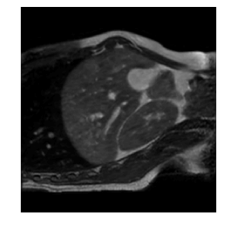

With this motivation, [6] proposed a convolutional neural network (CNN) based approach for temporal interpolation of navigators. Their CNN takes as inputs a fixed number of acquired images and learns to predict the missing images directly in the intensity space. This approach, which we call the Simple Convolutional Interpolation Network (SCIN), is a ’black-box’ formulation that does not incorporate any prior information about the interpolation process. Image prediction is guided only by the cost function used to optimize the network parameters. The issue with this is that it is unclear whether the image similarity measures that are generally used as cost functions suffice to ensure fidelity of the generated images to the original images. Indeed, Fig. 1b shows a case where an image interpolated using SCIN is quite blurry and misses several liver and lung structures present in the original image.

Figure 1: (a) Ground truth and (b,c) interpolated images from (b) baseline (SCIN) and (c) proposed method (MFIN). The image interpolated via SCIN is heavily blurred and misses several lung and liver structures, while the proposed method is able to preserve the details in the ground truth image.